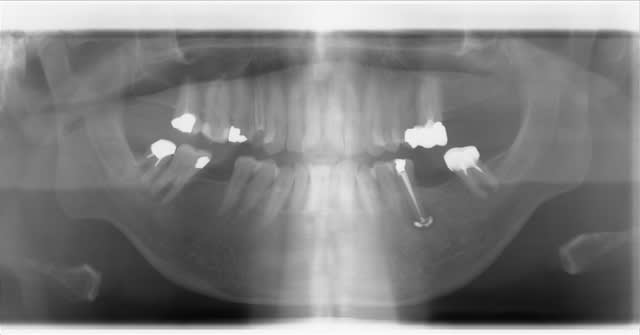

Patient vu à l'instant pour infection traitée il y a 3 semaines sur 35 et joyeux dépassement maintenant douloureux.

Vu aussi au dernier congrés SFOP lors d'une communication intitulée "Zorrodontologie" : avulsion d'une 46, retrait d'un instrument fracturé, obturation canalaire, réimplantation.

Moi je l'ai fait. Patiente que j'avais adressé à deux chir pour résection apicale pour une 46, ils ont refusé. Mobilité 3. Beau foyer apical. RTE du tiers apical impossible.

Un an après, pas d’ankylose, guérison totale du foyer apical.